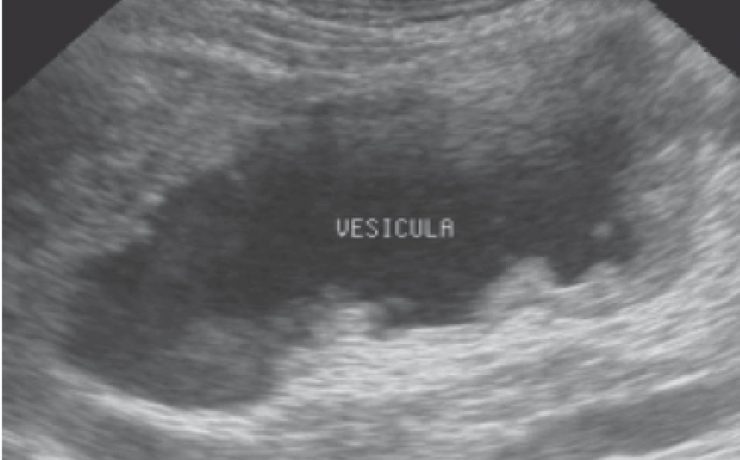

ABORDAJE QUIRÚRGICO DE NÓDULOS MAMARIOS DURANTE EL EMBARAZO

Los nódulos mamarios descubiertos durante el embarazo representan serio problema clínico el retraso en el diagnóstico de cáncer de mama en el embarazo puede aumentar la mortalidad perinatal. El cáncer de mama diagnosticado durante el embarazo en el puerperio o en el primer año posterior al nacimiento se considera asociado